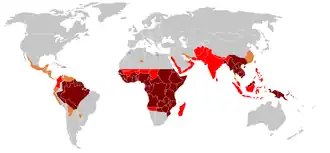

A malária é endémica em regiões tropicais e subtropicais devido à chuva abundante, temperatura quente e grande quantidade de água estagnada, o que proporciona habitats ideais para as larvas do mosquito. A doença encontra-se disseminada pelas regiões tropicais e subtropicais do planeta ao longo de uma larga faixa em redor do equador,[1] que inclui grande parte da África subsariana, Ásia e América Latina.[2] Em 2016, ocorreram em todo o mundo 216 milhões de casos de malária, que se estima terem sido a causa de 731 000 mortes.[3][4] Cerca de 90% dos casos e das mortes ocorreram em África.[7] Entre 2000 e 2015 a incidência da doença diminuiu 37%.[7][8] A malária está geralmente associada à pobreza e tem um grande impacto negativo no desenvolvimento económico.[9][10] Em África, estima-se que a doença resulte em perdas de 12 mil milhões de dólares por ano devido aos custos com a prestação de cuidados de saúde, baixas de trabalho e impacto no turismo.[11]

♦ Ocorrência de malária resistente à cloroquina

♦ Sem ocorrência de ‘’Plasmodium falciparum ou resistência à cloroquina

♦ Sem malária

A malária é atualmente endémica nas regiões equatoriais, em regiões da América, algumas partes da Ásia e grande parte de África. Entre 85 e 90% das mortes por malária ocorrem na África subsariana.[94] Em 2009, uma estimativa indicou que os países com a maior taxa de mortalidade por cada 100 000 habitantes foram a Costa do Marfim (86,15), Angola (56,93) e o Burkina Faso (50,66).[95] Em 2010, uma outra estimativa indicou que os países com maior taxa de mortalidade foram o Burkina Faso, Moçambique e o Mali.[91] Ainda em 2010, cerca de 100 países possuíam malária endémica.[89][96] Estes países são visitados anualmente por mais de 125 milhões de viajantes internacionais, dos quais mais de 30 000 contraem a doença.[52]

Na Europa e na América do Norte, a doença está praticamente erradicada. Entre 1993 e 2003, a malária provocou a morte a 900 pessoas na Europa.[52] Em 2011 houve apenas 102 casos adquiridos in loco, restritos a cinco países.[97] Em Portugal, os últimos casos de Malária adquirida no país foram diagnosticados em 1959, e desde então a totalidade das ocorrências são casos importados por pessoas que visitaram países tropicais. Em 2011 foram notificados 58 casos importados de Malária.[98]

No Brasil, 97% dos casos ocorrem na região amazónica e pouco menos de 2,9% nas regiões próximas, sendo mais de 80% nas regiões rurais.[99] Em Moçambique, a malária é a principal causa de morte infantil. No entanto, entre 2006 e 2012 o número de casos de malária tem vindo a diminuir significativamente. Em 2006 registaram-se 6,5 milhões de casos, os quais provocaram 5 053 mortes,[100] enquanto que em 2012 se registaram apenas 3,1 milhões de casos e 1 653 mortes.[101] Em Angola, o número de casos também tem vindo a diminuir. Entre 2006 e 2010, registaram-se em média quatro milhões de casos por ano, enquanto que em 2011 se registou pela primeira vez um número inferior a três milhões.[102]

A distribuição geográfica da malária nas regiões de grande dimensão é complexa. Há muitos casos de regiões endémicas e regiões livres de malária que estão muito próximas entre si.[103] A malária é prevalente em regiões tropicais e subtropicais devido à chuva intensa, temperatura elevada constante e humidade elevada, factores que proporcionam água estagnada em abundância propícia à reprodução contínua de larvas de mosquito.[104] Em regiões mais secas, é possível prever com alguma precisão os surtos de malária através da previsão meteorológica da ocorrência de chuva.[105] A malária é mais frequente nas áreas rurais do que em área urbanas. Por exemplo, há várias cidades na bacia do rio Mekong que são livres de malária mas a doença é prevalente em muitas das regiões rurais.[106] Por outro lado, em África a malária está presente tanto em áreas rurais como urbanas, embora o risco seja menor nas maiores cidades.[107] É provável que as alterações climáticas venham a criar novos habitats para o mosquito vetor de malária em regiões mais frias e de maior altitude, provocando alterações na sua distribuição geográfica e o aumento de surtos epidémicos.[108]